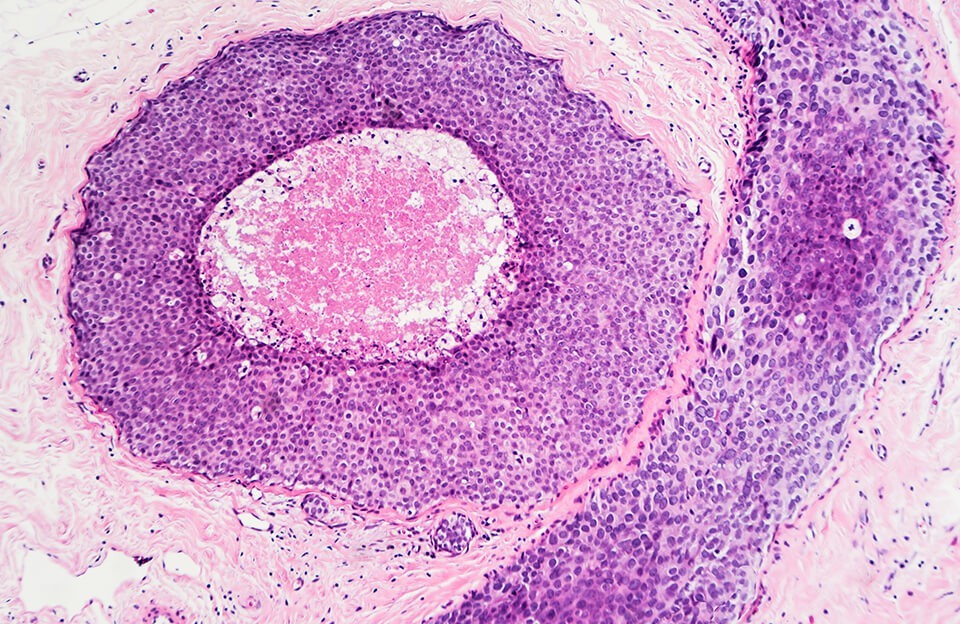

Хронический миелолейкоз (ХМЛ) представляет собой злокачественное заболевание крови, характеризующееся избыточным производством миелоидных клеток в костном мозге. Врачи отмечают, что основная причина развития ХМЛ связана с хромосомной аномалией, известной как Philadelphia-хромосома, которая возникает в результате транслокации генов. Симптомы заболевания могут включать усталость, потерю веса, ночные поты и увеличение селезенки. Важно отметить, что на ранних стадиях болезнь может протекать бессимптомно, что затрудняет диагностику. В лечении ХМЛ применяются таргетные препараты, такие как иматиниб, которые направлены на подавление аномальных клеток. Врачи подчеркивают важность регулярного мониторинга состояния пациента и своевременной коррекции терапии, что позволяет значительно улучшить прогноз и качество жизни больных.

Хронический миелолейкоз (ХМЛ) представляет собой злокачественное заболевание крови, характеризующееся избыточным производством миелоидных клеток в костном мозге. Врачи отмечают, что основная причина развития ХМЛ связана с хромосомной аномалией, известной как Philadelphia-хромосома, которая приводит к образованию аномального белка BCR-ABL. Симптомы заболевания могут включать усталость, потливость, потерю веса, боли в костях и увеличение селезенки. Важно, что многие пациенты могут не испытывать выраженных симптомов на ранних стадиях. Лечение ХМЛ в основном включает таргетную терапию с использованием ингибиторов тирозинкиназы, что значительно улучшает прогноз и качество жизни пациентов. Врачи подчеркивают важность ранней диагностики и регулярного наблюдения для достижения наилучших результатов.

Хронический миелолейкоз (ХМЛ) — это тип рака крови, который возникает из-за аномальных изменений в стволовых клетках костного мозга. Он характеризуется избыточным производством миелоидных клеток, что приводит к накоплению незрелых клеток в крови. Развитие заболевания связано с хромосомной аномалией, известной как Philadelphia-хромосома, которая возникает в результате транслокации между 9-й и 22-й хромосомами.